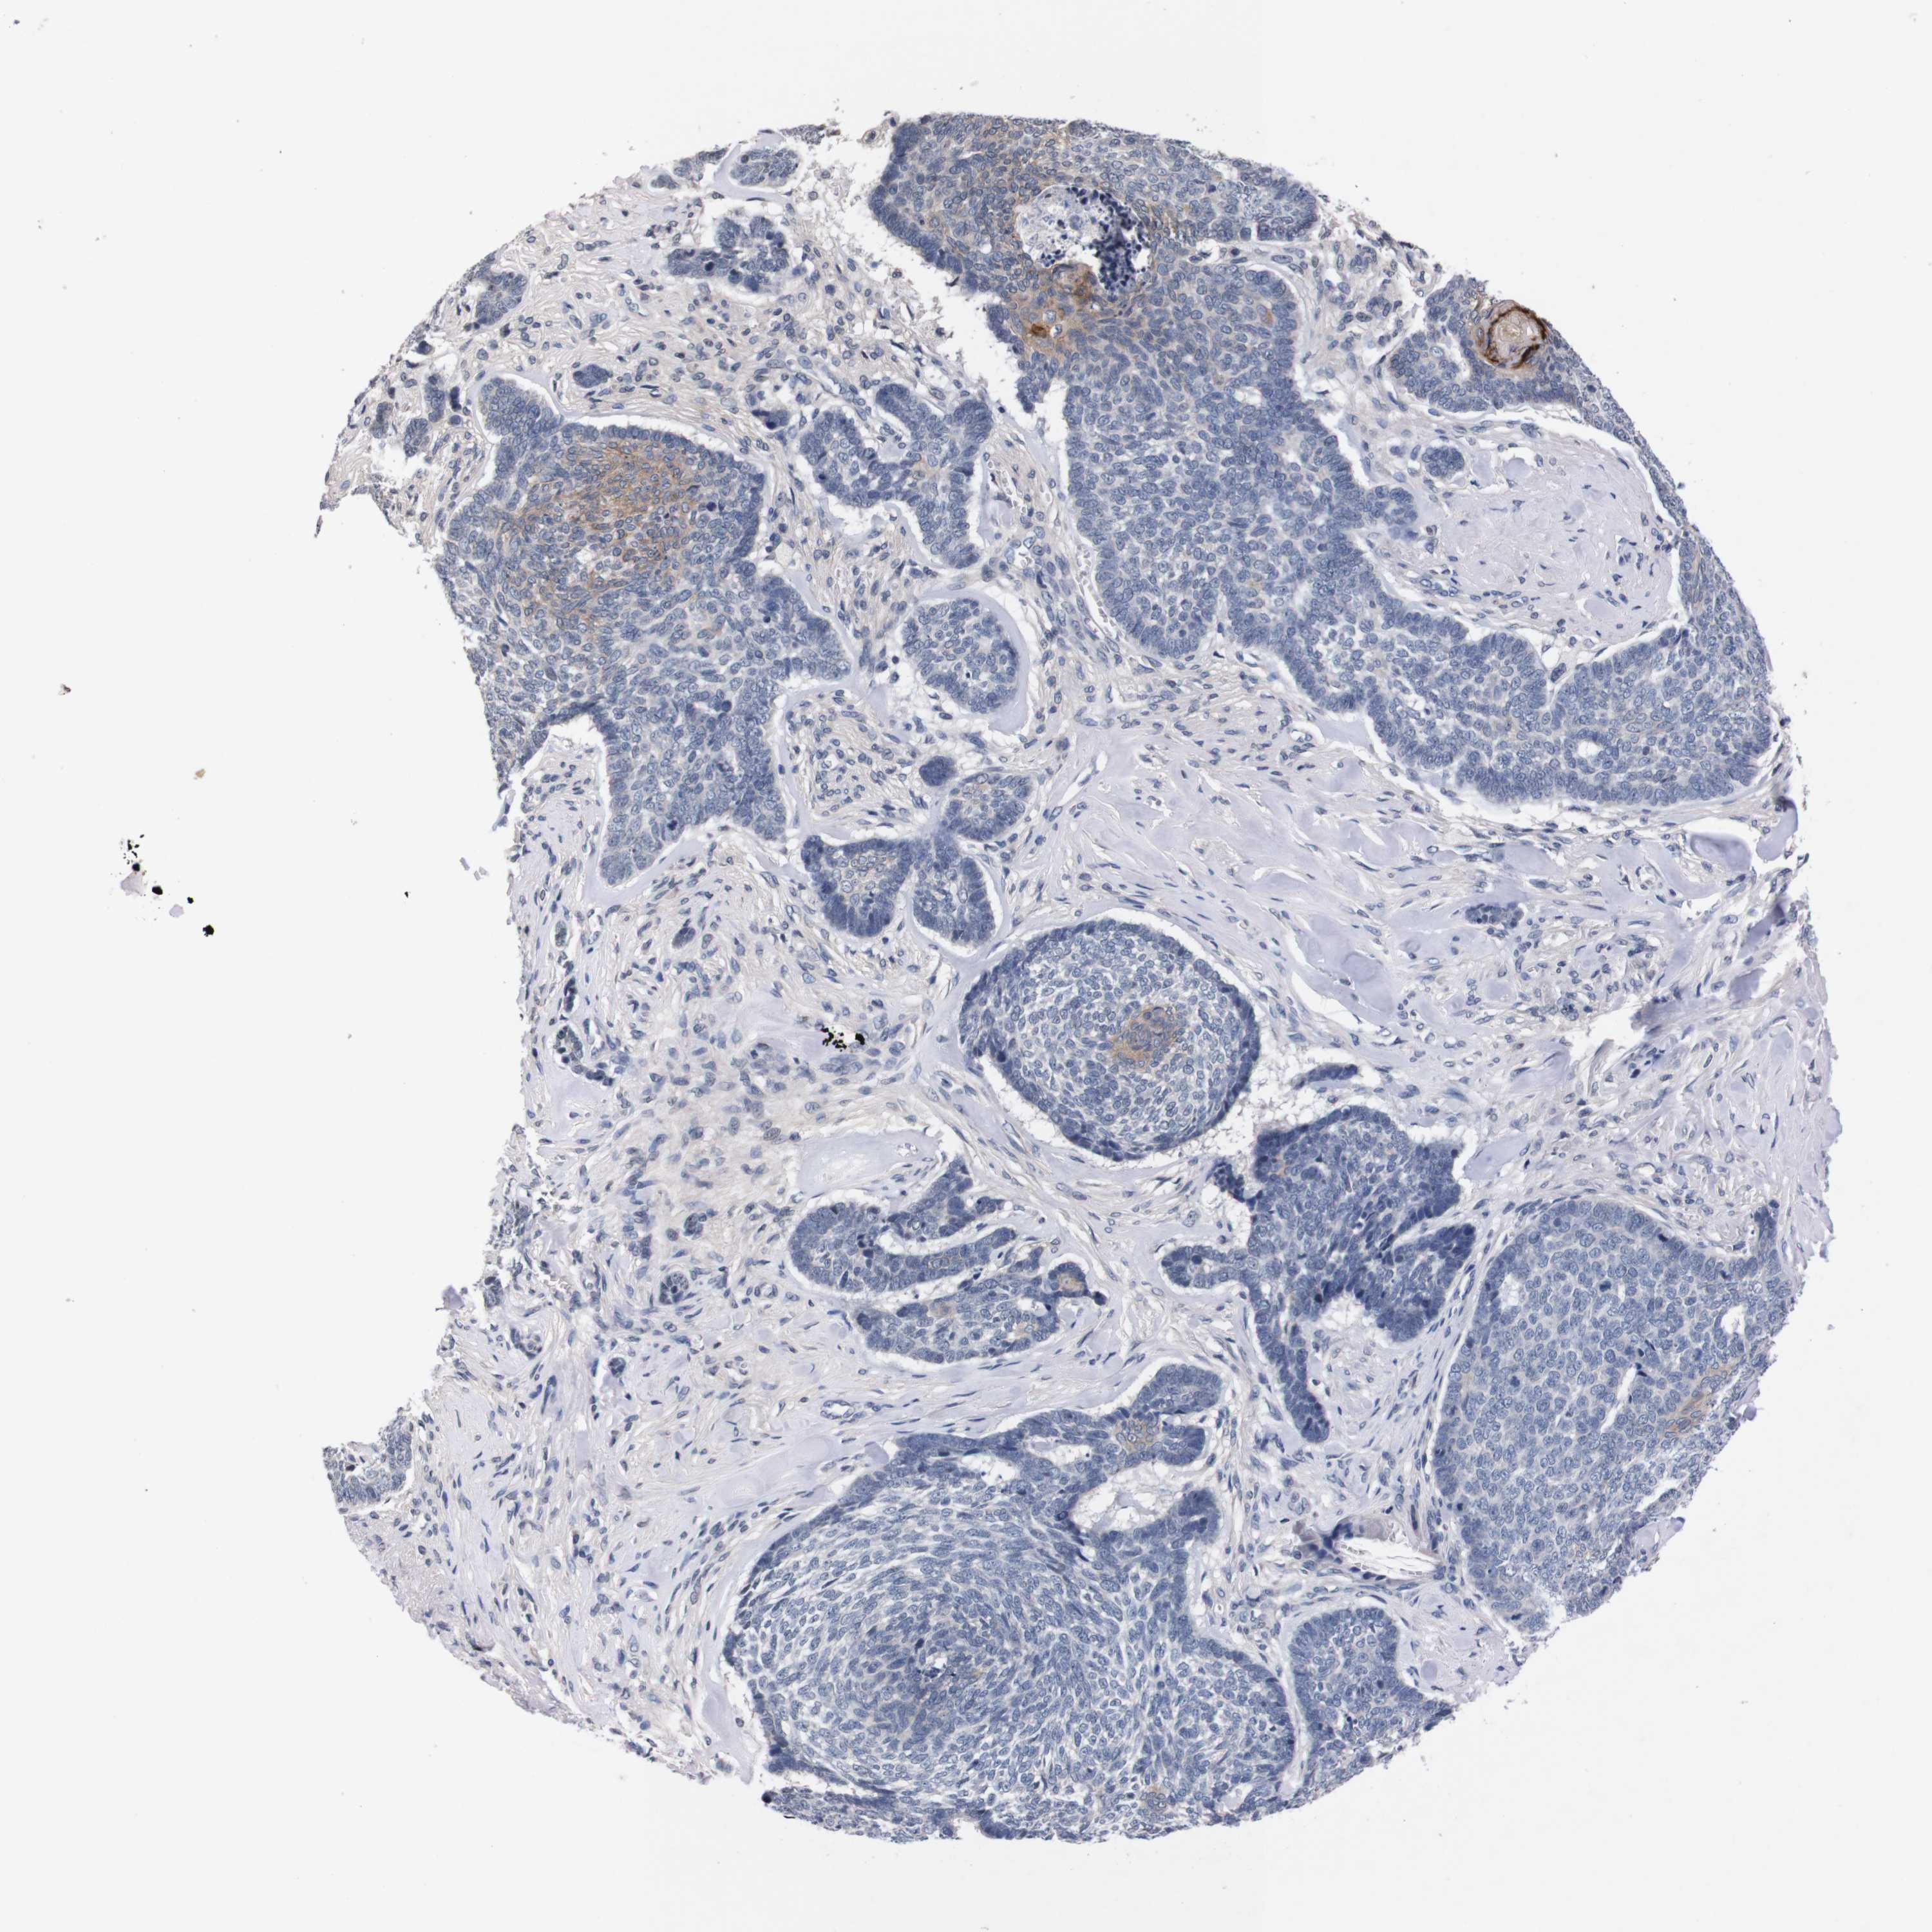

SKIN CANCER - Protein expressioni

A mouse-over function shows sample information and annotation data. Click on an image to view it in a full screen mode. Samples can be filtered based on level of antibody staining by selecting one or several of the following categories: high, medium, low and not detected. The assay and annotation is described here.

Antibody stainingi

Antibody staining in the annotated cell types in the current human tissue is reported as not detected, low, medium, or high, based on conventional immunohistochemistry profiling in selected tissues. This score is based on the combination of the staining intensity and fraction of stained cells.

Each image is clickable and will lead to virtual microscopy that enables deeper exploration of all samples and also displays staining intensity scores, fraction scores and subcellular localization as well as patient and tissue information for each sample.

Antibody HPA006746

Antibody CAB009805

Squamous cell carcinoma, metastatic, NOS

Basal cell carcinoma